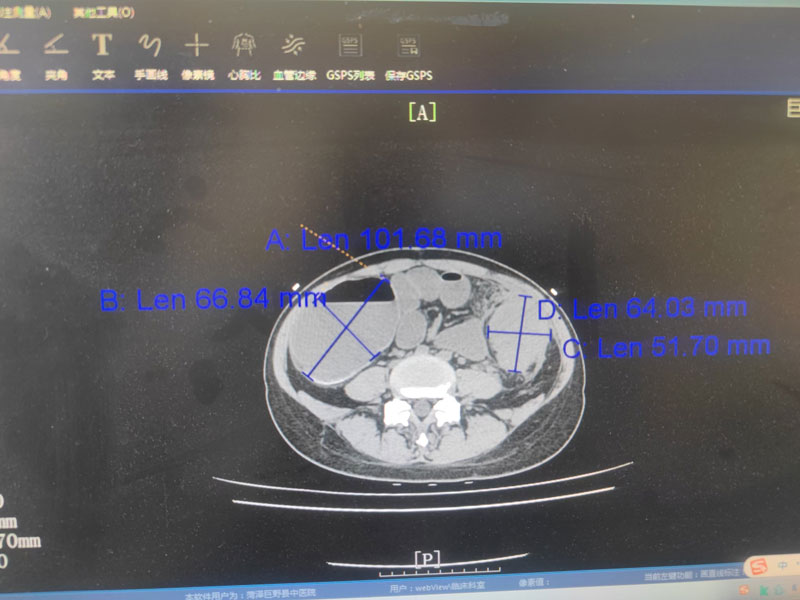

巨野县中医医院外一科成功实施急诊术中结肠灌

2025-02-22

新春伊始,我院外一科收治了一位急性腹痛肠梗阻患者,经检查,在患者左下腹触及质硬巨大包块,直径超10厘米!!腹部CT显示,降结肠肠壁明显增厚,肠腔结构不清,近端升结肠和横结肠明显扩张,肠壁变薄。外一科赵加...